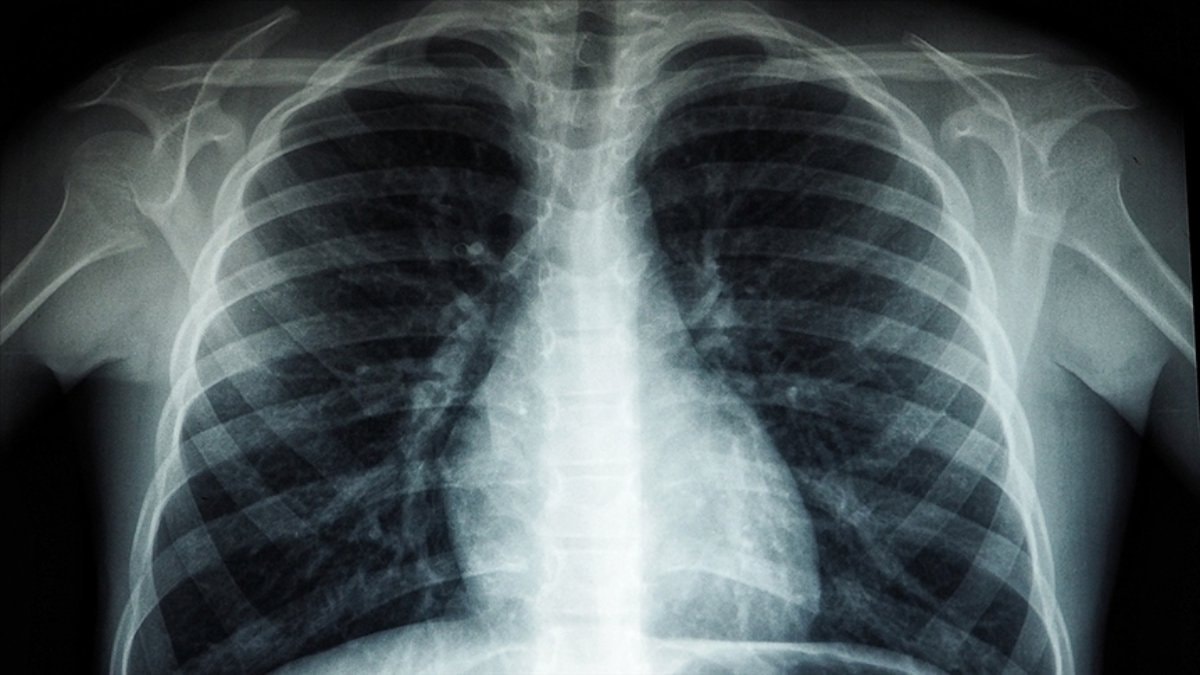

Beyaz akciğer sendromu nedir

Bu sendromu, akciğerlerin ani bir şekilde iltihaplanması sonucu oluşan, hayati organlara yeterli oksijen gitmeyen ciddi bir durumdur.

Silika tozlarına uzun süre maruz kalan kişilerde gelişebilir.

Akciğerde kalsiyum birikirse (kalsiyum oksit, kalsiyum karbonat, kalsiyum sülfat gibi kimyasallara uzun süreli maruz kalınan mesleklerde) akciğer filminde beyaz lekelenmeler görülür.